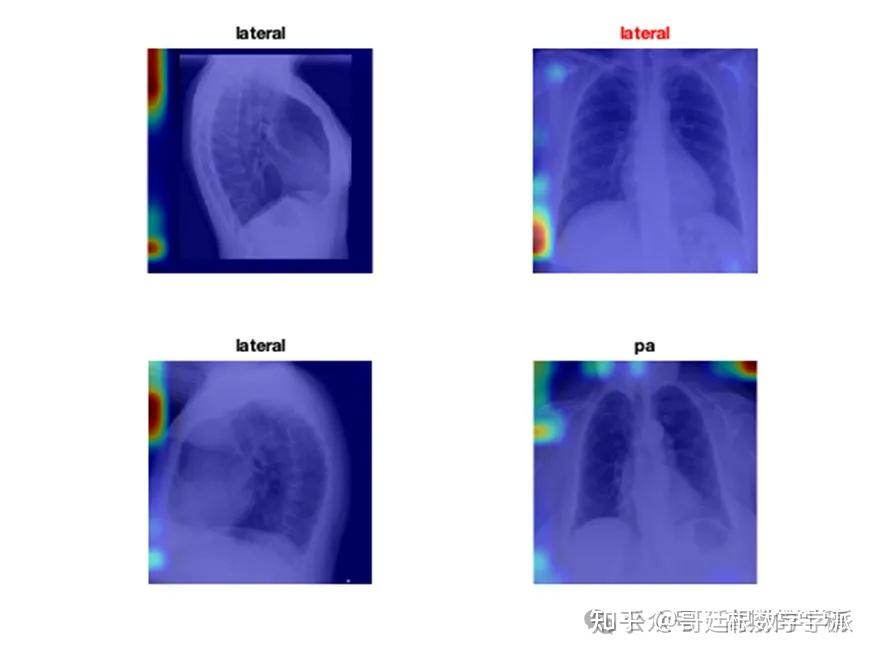

医学图像的深度学习可解释性(MATLAB R2021B)